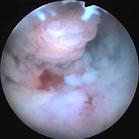

子宮頸內膜凡借細長的蒂附著於子宮腔內壁的腫塊,臨床上都可稱為子宮息肉。 因此,在宮腔內的息肉樣腫塊,可能是有蒂的黏膜下肌瘤、子宮內膜息肉、子宮腺肌瘤樣息肉和惡性息肉(癌或肉瘤)。 主要症狀為月經量增多或不規則子宮出血;宮頸口處看到或觸及息肉,子宮體略增大;作宮腔鏡檢查或分段診刮,將取出的組織或摘除的息肉送病理檢查,可以明確診斷,並可與功能失調性子宮出血、黏膜下子宮肌瘤及子宮內膜癌等鑑別。

子宮頸內膜主要症狀為月經量增多或不規則子宮出血;宮頸口處看到或觸及息肉,子宮體略增大;作宮腔鏡檢查或分段診刮,將取出的組織或摘除的息肉送病理檢查,可以明確診斷,並可與功能失調性子宮出血、黏膜下子宮肌瘤及子宮內膜癌等鑑別。